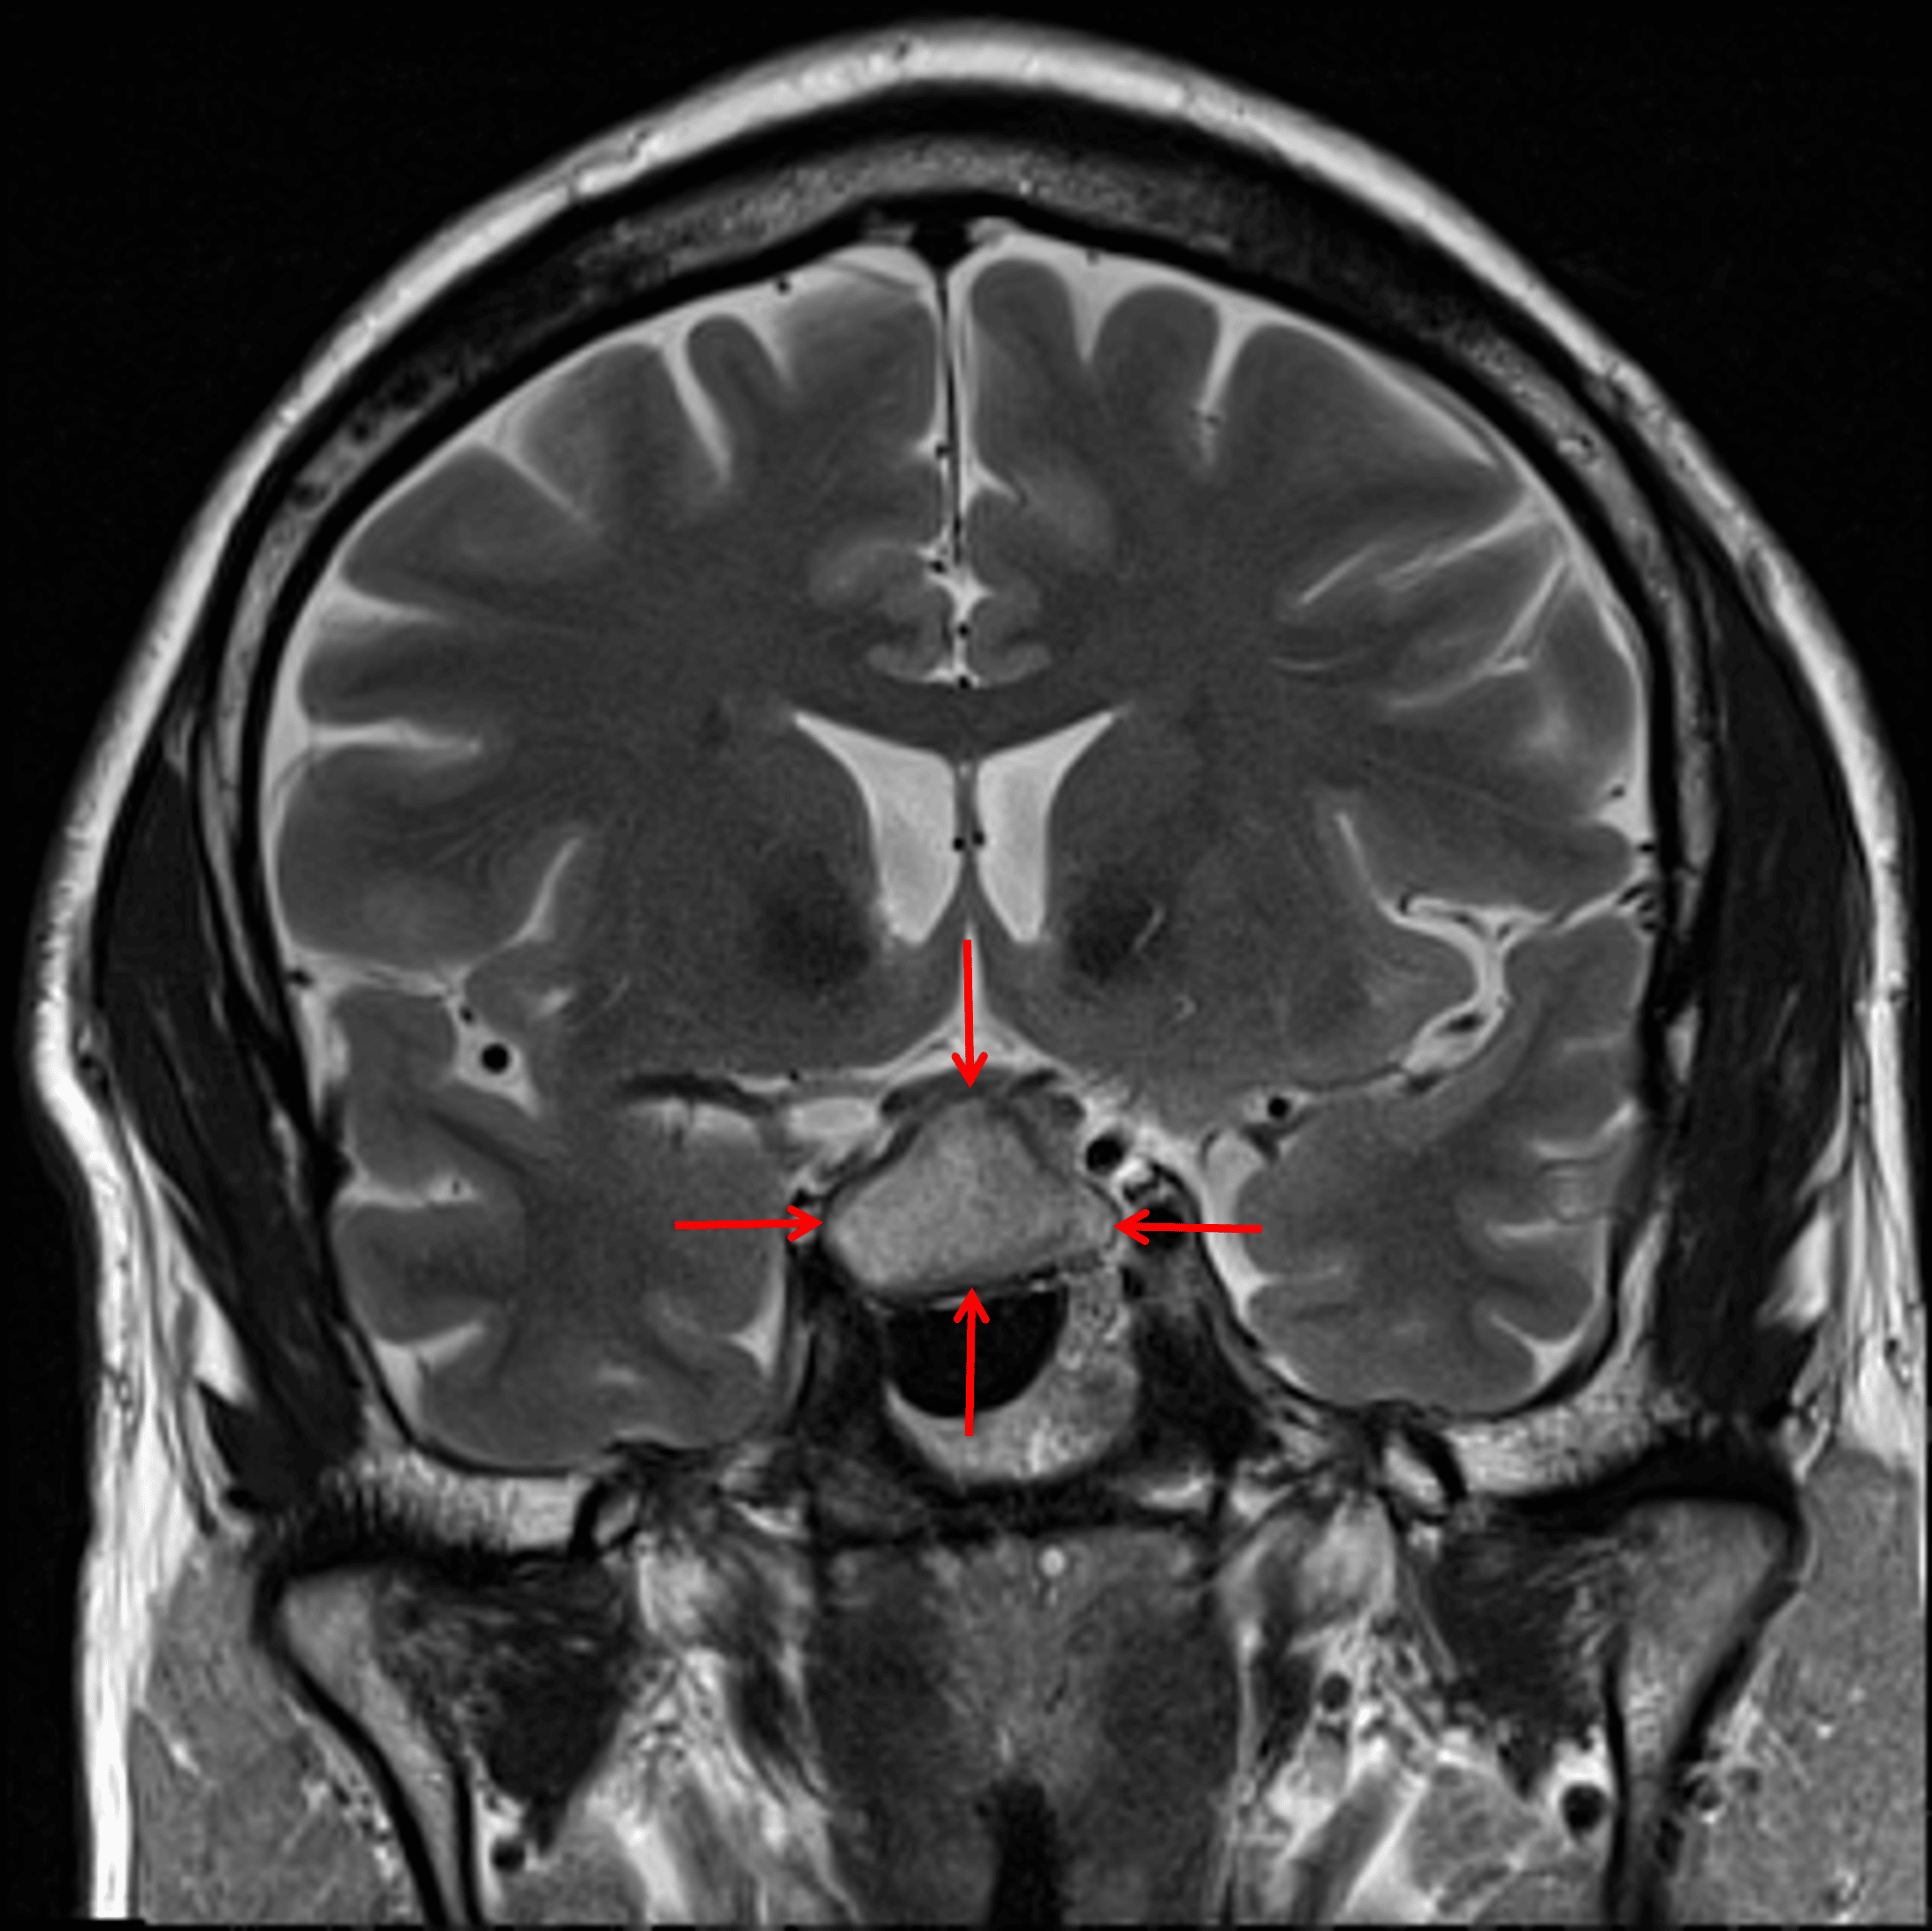

• Peripherally-enhancing sellar/suprasellar mass measuring 2.5 x 1.6 x 1.7 cm, which is not separable from the pituitary gland

• Centrally, the lesion is mildly T1 hypointense and T2 hyperintense

Cystic sellar/suprasellar mass with internal T2 signal hyperintensity (red arrows).